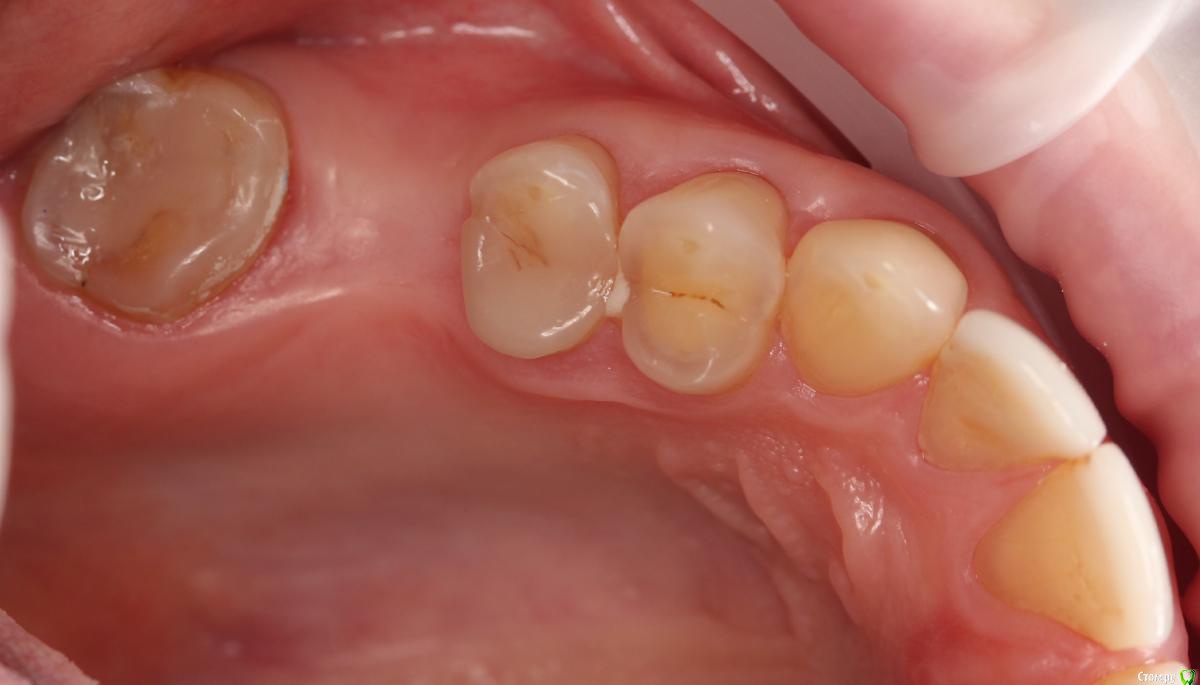

Dmitry DK Опубликовано 10 сентября, 2019 Поделиться Опубликовано 10 сентября, 2019 Фотопротокол к сожалению не полный, но ничего особенного и не проводилось. 1) Открытый синус, удален пломбировочный материал из пазухи, уложен 1 г Bio-oss 2) через 6 мес имплантация Straumann SP 4.1\10 Результат через год 9 Ссылка на комментарий